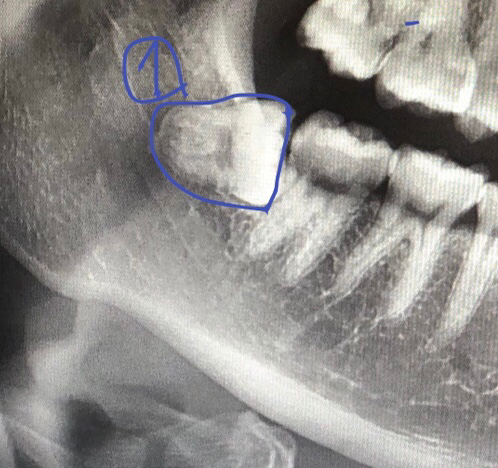

현재 사랑니가 매복되어 있고 기울어 있어 난이도가 높은 발치입니다. 따라서 반드시 매복사랑니 발치 경험이 풍부한 구강외과 전문의에게 치료를 받길 권합니다.

매복 사랑니라서 뽑을때 시간도 좀 걸리고 잇몸도 크게 열고 뼈 삭제도 해야되기 때문에 통증도 조금은 심할것같긴합니다.

사랑니가 마찬가지로 깊이 매복되어 있는 편이기 때문에 발치 시에 통증을 느낄 수 있습니다.